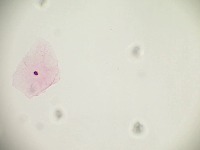

Cervical Cancer Screenings: The "PapDetector" can be used for the initial screening in detecting cervical cancer. Its ability to classify different cellular structures could provide invaluable assistance in large-scale cervical cancer screening tests, making the entire process more efficient.

Medical Research: Scientists and researchers can use this model to identify and further study these cellular structures. This could improve the understanding of various conditions related to cell abnormalities, thus leading to new treatments or diagnostic methods.

Training Medical Students: The "PapDetector" can also serve as a learning tool for medical students, enabling them to visually learn and identify cell structures that denote normal and abnormal cases.

Pharmaceutical Development: The computer vision model could be utilized in the pharmaceutical industry to screen the effects of drug treatments on cell morphology – highlighting normal, HSIL, LSIL, ANORMAL, Koilocytes changes in response to pharmaceutical compounds. This information would be useful in drug development and efficacy trials.